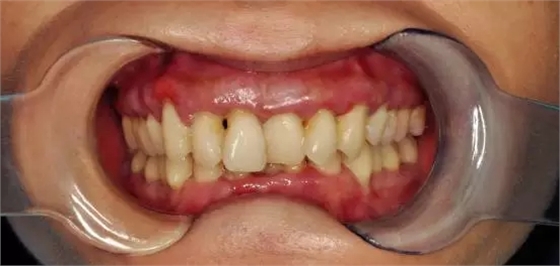

陸小姐,35歲,患者數(shù)月前發(fā)現(xiàn)下前牙松動,進(jìn)食時疼痛,刷牙出血;

檢查:全口口腔衛(wèi)生差,牙結(jié)石嚴(yán)重,牙齦紅腫,探之出血牙齒三度松動,前牙牙根暴露,X片顯示牙槽骨吸收嚴(yán)重

診斷:牙周炎(重度)

建議:全口清潔、齦下刮治,牙周治療

處理:洗牙、拋光、上藥